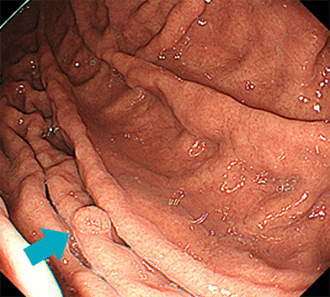

胃過形成性ポリープピロリ菌に感染している萎縮性胃炎を背景に発生することが多く、感染の指標にも成り得るといえます。また広義の腺窩上皮型過形成ポリープには、血管・間質の増生を伴わない単純な腺窩上皮の増殖によるポリープもあります。このようなものはピロリ菌未感染胃や除菌後胃に見られることも多く、春間-川口病変(多発性白色扁平隆起)として区別されています。

春間-川口病変はほとんどの場合で多発します。

胃腺腫胃カメラ(胃内視鏡検査)の施行時に、偶然みつかることがほとんどです。健診・胃がん検診でのバリウム検査が、発見契機になることも多いです。胃底腺ポリープや過形成ポリープのほとんどは、内視鏡観察での鑑別が可能です。胃底腺ポリープは周囲粘膜と同じ色調の、つるつるとした無茎性~亜有茎性の数mm程度のことが多い病変です。対して過形成ポリープは赤みの強いやや凹凸のある表面をした、亜有茎性~有茎性のこともあるポリープです。胃底腺ポリープではがん化は非常にまれで、過形成ポリープでも通常は2cmを超えない場合での担がんは比較的まれです。しかしながら小さくても形態からラズベリー様腺窩上皮型胃腫瘍(ラズベリー型胃がん)との鑑別を要すことがあります。そのため通常は胃底腺ポリープ・過形成ポリープでは生検での組織病理学的検査を要することは少ないですが、上記のような場合や、家族性大腸腺腫症(FAP)に生じる胃底腺ポリープなどではがん化していないかをみるために、生検を要することがあります。